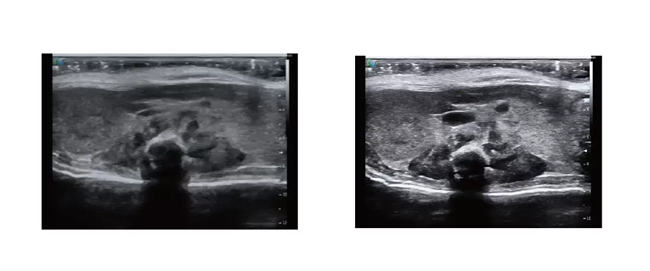

Sonorover UR820 超高频小动物超声成像系统 搭载了先进的高分辨率成像平台与高频探头,并且融合了最前沿的超声成像技术,以卓越的图像质量,引领行业标准。全面满足小动物心血管、腹部 脏器、肿瘤、胚胎等生物医学研究领域的需求,助力科研人员在探索未知的道路上不断前行。

成像效果展示

文献和实验1、【仪器名称】:小动物超声成像系统。 2、【仪器型号】:Vevo 770。 3、【生产厂家】:visualsonics Co. Ltd. 4、【检测适用范围】:该系统为一套小动物灰阶及血流参数的影像系统,用来进行小动物胚胎及肿瘤血流的评估。利用高频超音波精细的分辨率对人体及小动物各表层组织的观察已经开始被广泛的应用